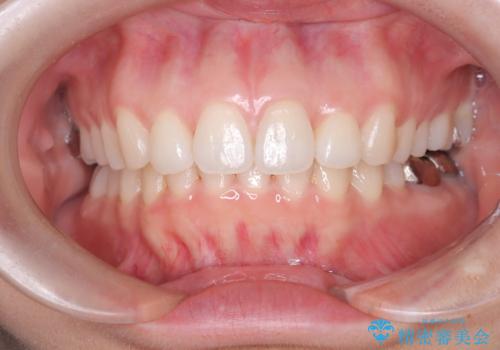

審美装置を用いたワイヤー矯正|非抜歯で歯の凸凹を改善

治療では、白いブラケットとホワイトワイヤーを使用し、矯正装置が目立ちにくいよう配慮しました。歯列を拡大しながら適切に歯を移動させ、IPRを併用することで、無理なくスペースを確保しました。見た目に配慮しながら、歯の凸凹をスムーズに整え、噛み合わせも改善。患者様からは「装置が思ったより目立たず、歯並びがきれいになって嬉しい」との声をいただきました。